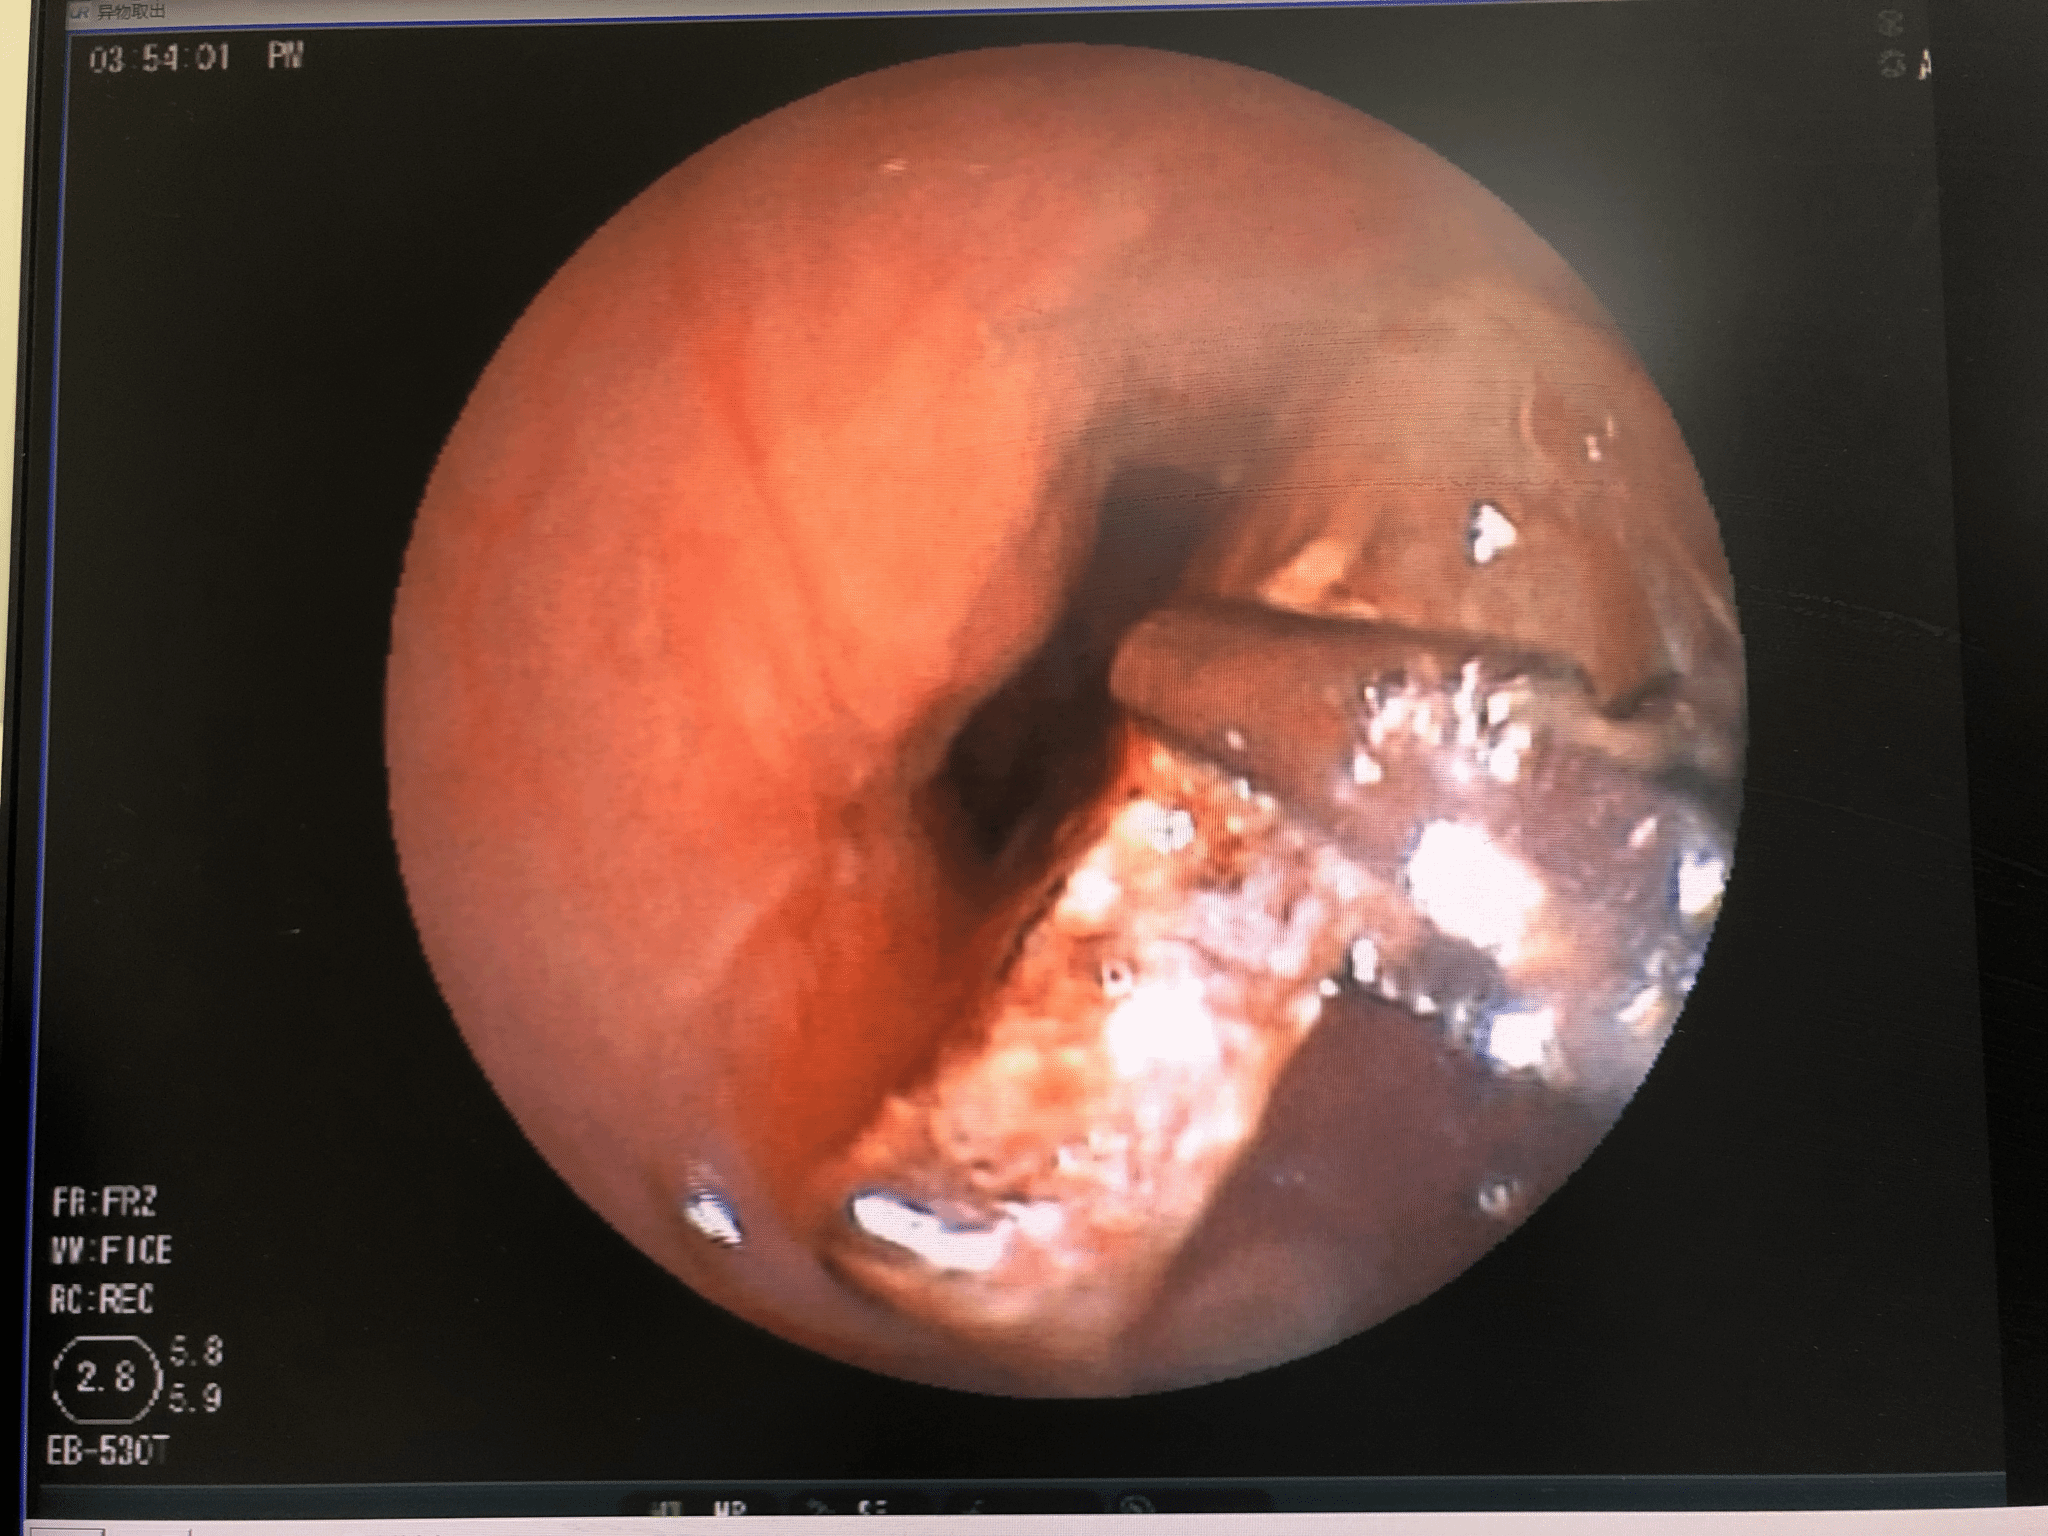

异物取出术

异物取出前 异物取出中